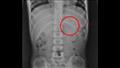

وكشفت فحوصات الأشعة السينية لصدر وبطن الطفل عن وجود قلم رصاص عالق في معدته، لذا أخبره الطبيب بالإكثار من السوائل، ، ولم يسمحوا له بتناول أي شيء سوى الموز لتسهيل عملية إزالة القلم من أمعائه.

أظهرت الأشعة السينية لاحقا أن قلم الرصاص تحرك من المعدة ليصل إلى "اللفائفي الأعوري"، وهو صمام عضلي يفصل بين الأمعاء الدقيقة والغليظة.